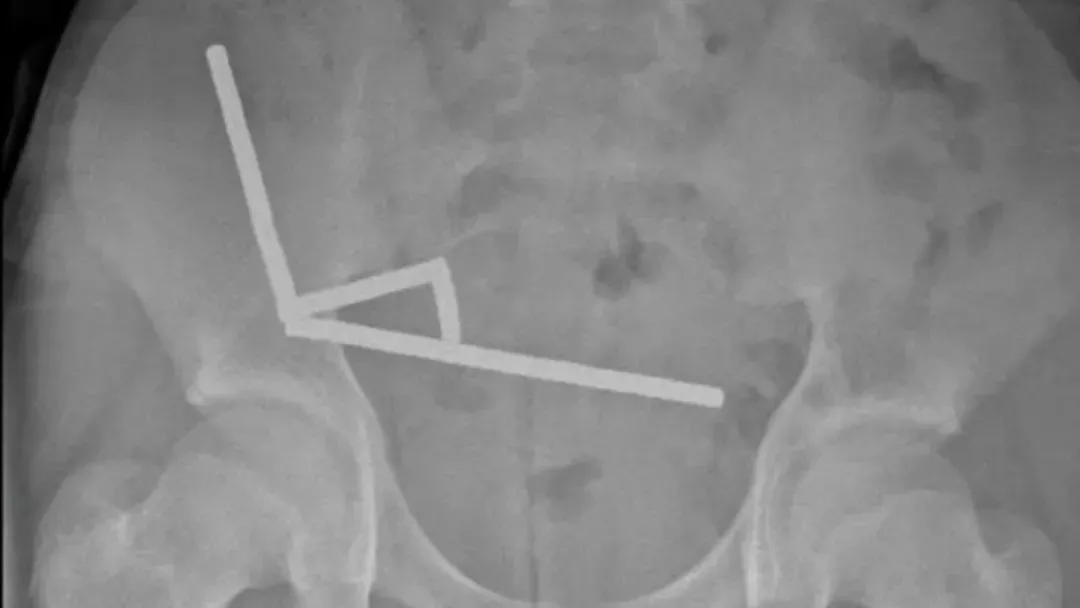

医生通过 X 光片观察到,男孩肠道的不同部位出现了四条线状的磁铁链。

腹部 X 光片显示了磁铁分布情况 来源:Lekamalage et al.,?NZMJ, 2025

200 颗磁铁在患儿腹中形成了磁铁链。来源:Lekamalage et al.,?NZMJ, 2025